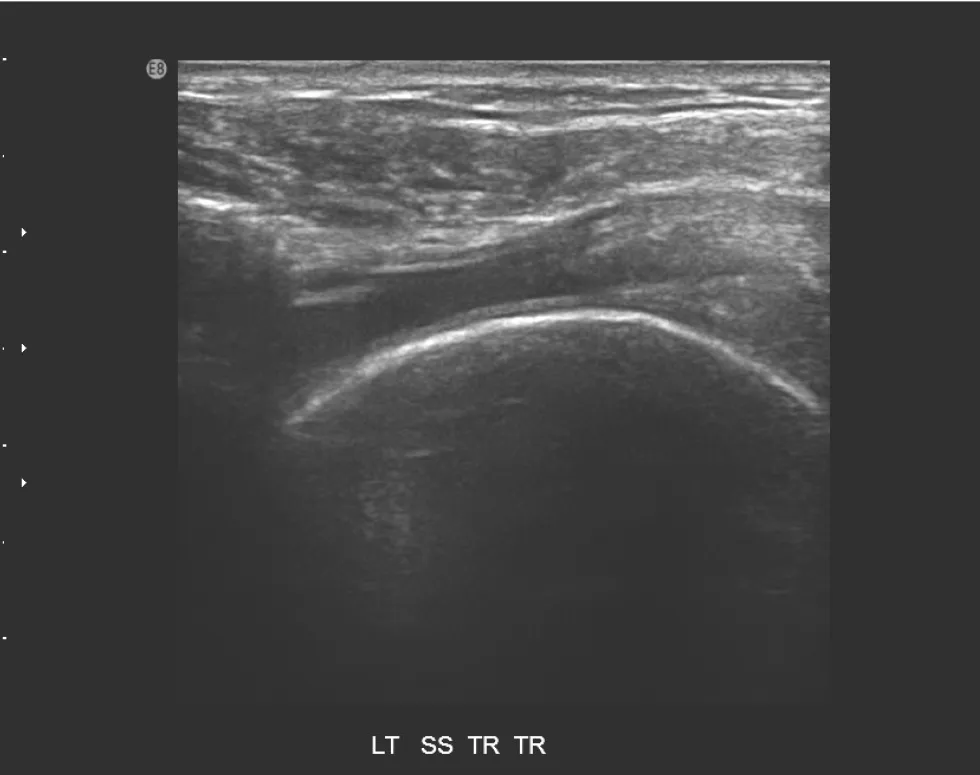

【106-1 醫學(六) 第72題】85歲女性患者,主訴左肩疼痛超過6個月,有局部壓痛,無肌肉萎縮現象,圖為左肩部超音波檢查,上圖為旋轉環帶長軸切 面,下圖為短軸切面,最可能之診斷為何?

詳解

破題關鍵

這題的解題核心在於辨識超音波影像中,棘上肌腱(supraspinatus tendon)出現的明顯缺損與纖維不連續性,這直接指向肌腱斷裂。

選項拆解

-A:錯在風濕性關節炎在超音波下主要表現為滑膜增厚、關節積液、骨侵蝕等,而非肌腱的局部斷裂缺損。